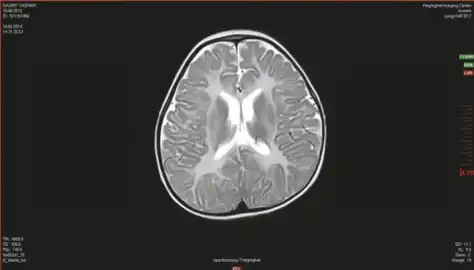

- Canavan’s disease demonstrates bilateral symmetric T2 white matter hyperintensity including involvement of the subcortical arcuate fibers